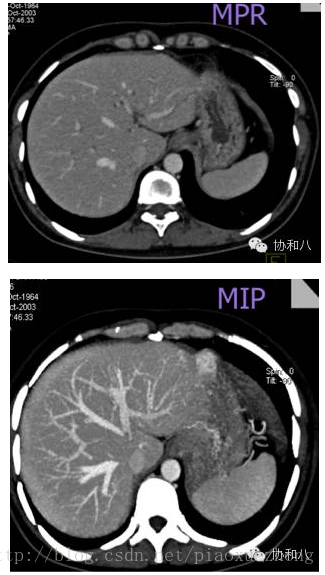

下面给大家比较下MPR和MIP的图像:

可以看到,MIP图像中的血管连续性更好。